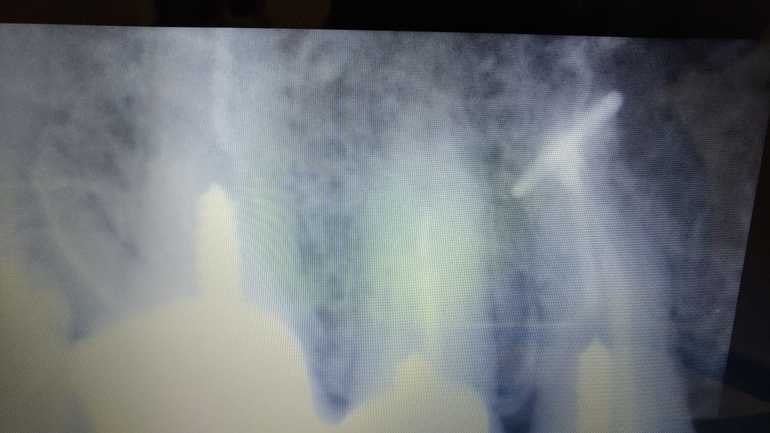

Инороднон тело на снимке зуба

Взрослые зубные проблемыДобрый день. Может кто сможет обьяснить, что это!?!? Стоматолог говорит, месяца через 2 переделаем снимок, должно рассосаться. Другой, что зуб только под удаление. Предыстория такова, был живой зуб, решили привести в эстетически красивый вид, в процессе работы решили зуб умертвить. Прочистили каналы, вставили штифт, нарастили. Над зубом, образовалось уплотнение, очень болезненное. Сделали снимок, а там что то непонятное. Как буква "Т"

Так похоже на инструмент.